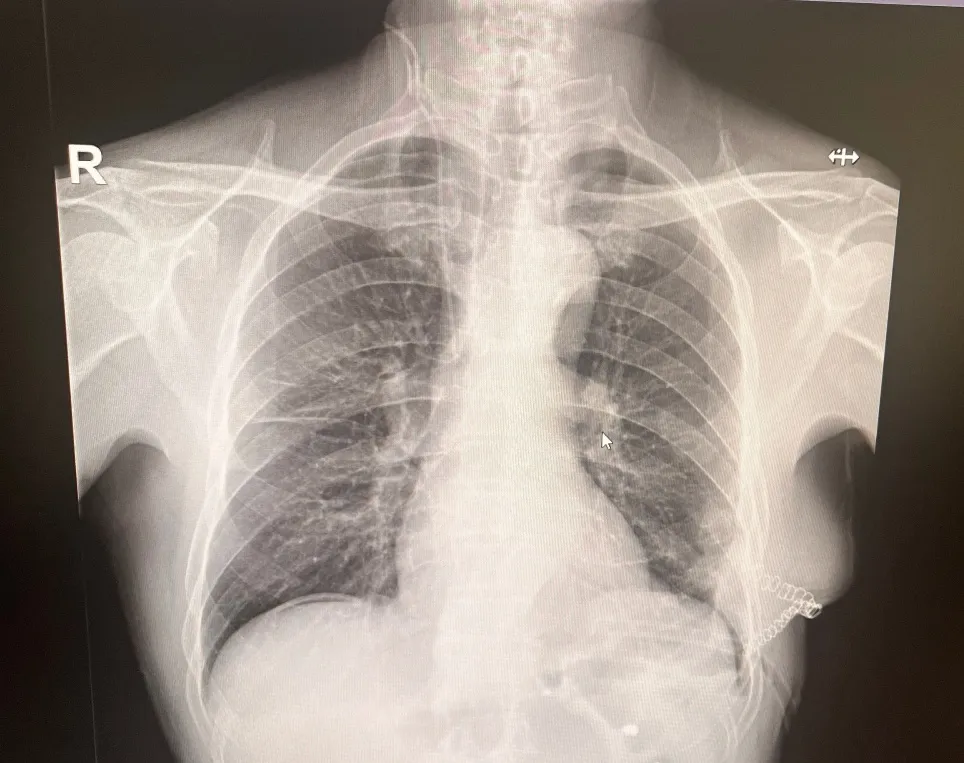

术前影像

辗转来到市二院胸外科,孙振教授在细致追问病史时,捕捉到一个关键细节:10年前,患者胸腹部曾被刀刺伤,当时仅做了外部缝合,未深入排查内部损伤。这一信息引起了孙振教授的高度警觉——很多陈旧性胸腹外伤虽表面愈合,却可能遗留膈肌破裂的隐患,并随时间推移发展为创伤性膈疝。腹部增强CT结果证实了这一判断。